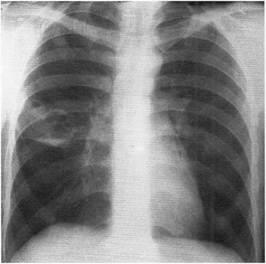

cavitate cu pereți subțiri umplut cu aer, dând cu umbra acoperite în interior și fiind descoperirea radiografică, caracteristic necomplicate pentru chist pulmonar închis inel. In prezenta simptomelor clinice caracteristice distrugerii pulmonare stafilococice astfel umbră indică formarea de degradare a cavității umplută cu aer, fundul care poate fi o cantitate mică de lichid (Fig. 1).

Fig. 1. X-ray a pacientului Ya 28 ani, într-o proiecție directă. În câmpul pulmonar mijlociu, se determină două cavități cu pereți subțiri, care măsoară 2x1,5 cm și 4x3,5 cm, umplută cu aer. O cantitate mică de lichid este detectată în partea inferioară a cavității mai mari. Distrugerea stafilococică a plămânilor